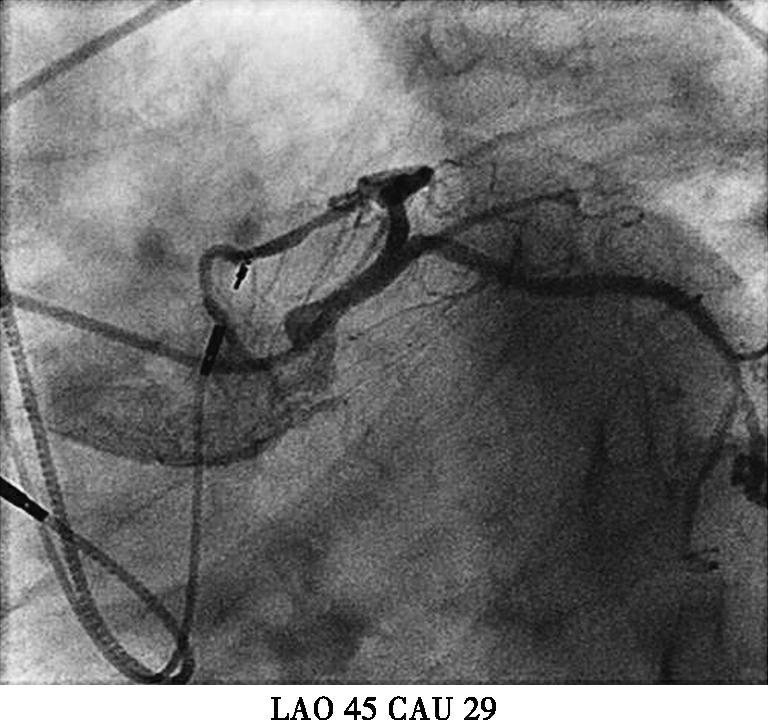

本例患者虽然有高血压、糖尿病等冠心病危险因素。起搏器电极植入后立刻发生的胸痛考虑与心绞痛关系不大,且患者未出现心电导联ST-T变化,胸痛原因主要考虑:起搏电极导致冠脉损伤?起搏电极刺破右室?遂台上决定立即行冠脉造影(图3);多个投照体位均可见起搏电极螺旋尖端触及前降支,因此决定行前降支血管内超声(IVUS)检查,结果于电极接触部位,血管8点钟方向可见强回声,距离血管外膜小于1mm;综合判断起搏电极损伤血管外膜导致胸痛的可能性大;随后进行电极重新植入,并再次造影排除起搏电极穿透冠脉可能,电极具体位置及冠脉造影见图4,心室起搏参数(阈值0.8V,阻抗670Ω,R波10.0mv)。患者症状完全消失,于导管室留观30分钟,复查心脏超声,心包内未见积液,排除起搏电极刺破右室可能,转回病房。

图3初次植入心室电极后冠脉造影